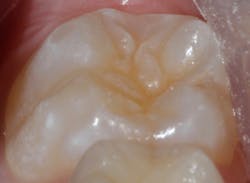

Sealant placement techniques should include complete isolation and an intermediary bonding layer (figure 1).25–29 The bonding layer and sealant curing can be one of two different methods: either placement and light-curing simultaneously in a simplified sealant technique or separately. Evidence-based studies show results favoring the individual light-curing technique in cases where conditions are dry and noncontaminated. In cases where there is saliva contamination, bond strength was the same in either simultaneous or individual light-cure placement methods.30–31